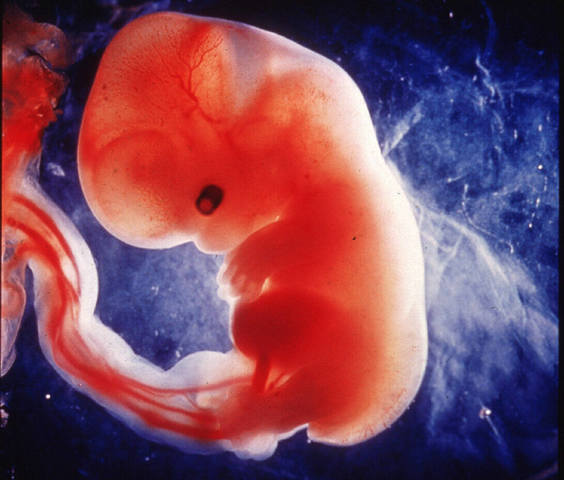

• Desarrollo Embrionario

Desarrollo Embrionario

Se extiende desde el momento de la fecundacion hasta el día 56 de vida intrauterina

• 3ra Semana

3ra Semana

El embrion mide 2mm, siendo un disco valado posee 3 hojas de tejido (disco embrionario trilaminar).